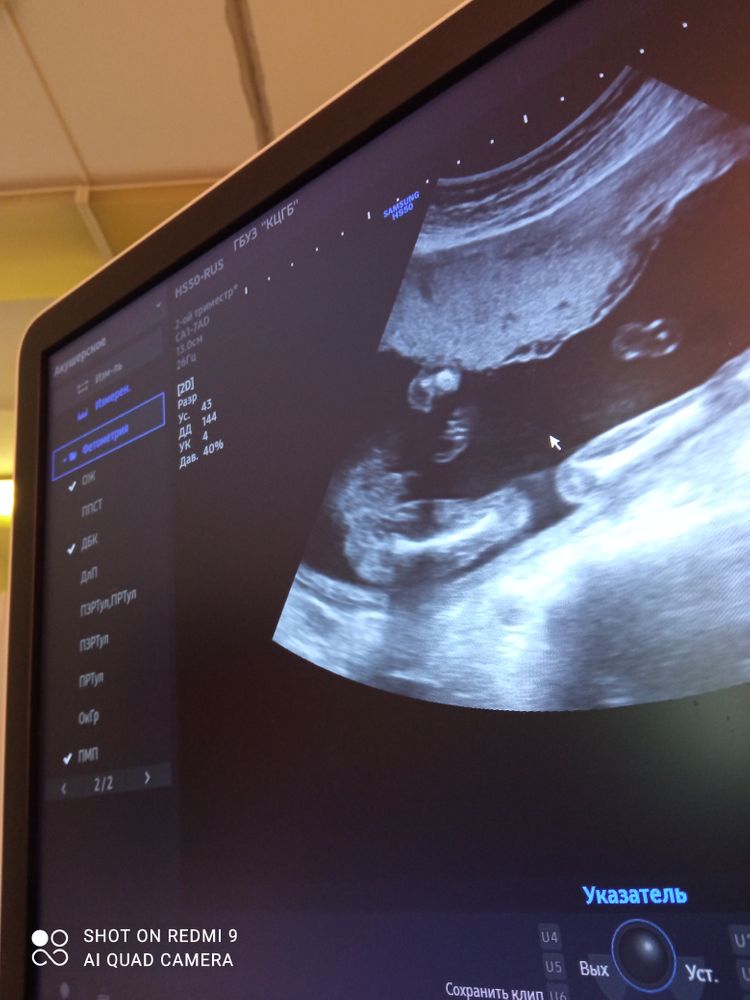

Врач сказал 100% мальчик

На вашем узи мальчик 100%, у девочки кофейное зернышко

Мне кажется, что на фото очень даже мальчик! 😊

Точно мальчик,девочки по-другому выглядят на узи

На фото 100000% пацан. Видно же) У нас 3 сына, ждём четвёртого сына😅